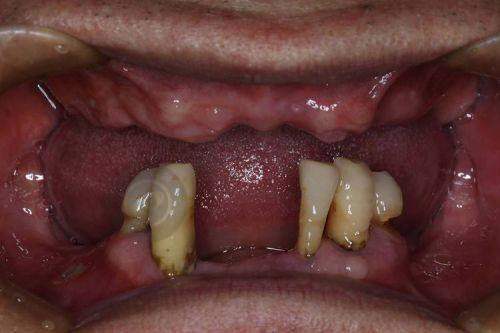

陕西省人民医院口腔科可开展全口数字化种植、ONLY 植骨术、骨劈开术、GBR 手术、即刻种植、上颌窦外提升等高难度的种植技术。